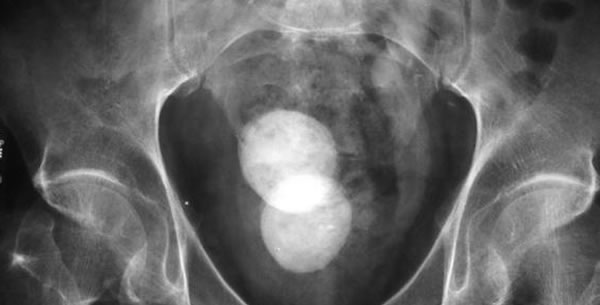

Što se veličine i oblika tiče oni jako mnogo variraju, pa mogu biti veliki kao teniska loptica ili još veći, a mogu biti vrlo sitni i tada ih je obično jako mnogo pa taj oblik nazivamo pijesak.

Kada je u jednoj šupljini više kamenaca oni se stružu jedni od druge pa stvaraju fasetirane plohe. Na presjeku pokazuju obično jednu od ove tri forme: